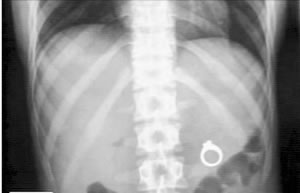

哈里斯当时和凯特琳还有一帮好友在餐厅吃饭,并偷偷把戒指放到了女友点的奶昔中,然后躲在一边希望拍下她发现戒指时的反应。不过凯特琳一时兴起,和女伴比起了看谁先吃完甜点,竟然毫无察觉地把整杯奶昔一饮而尽。哈里斯这下慌了神,急忙告诉女友奶昔里有戒指,可是凯特琳怎么都吐不出来。两个人只好赶往医院,X光片证实,凯特琳的确把戒指吞到了胃里。

原本浪漫温馨的求婚计划眼看就要泡汤,哈里斯灵机一动,在医院拿着X光片对着凯特琳跪了下来,并说出了那句练习了很久的话:“你愿意嫁给我吗?”幸运的是,女友答应了。